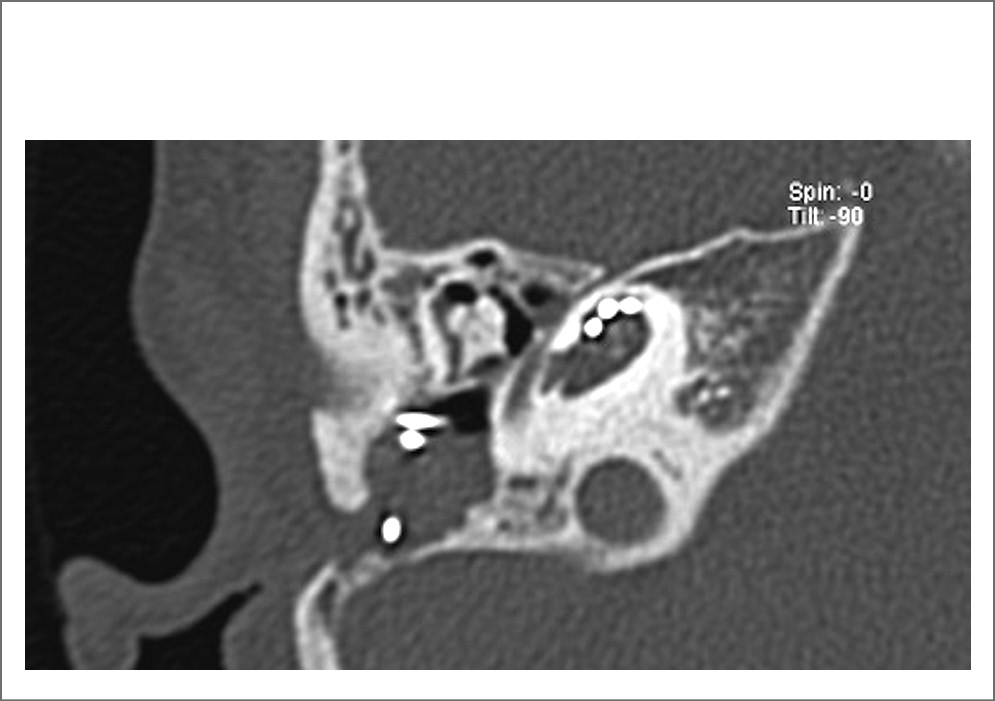

На КТ височных костей выявлена двусторонняя аномалия развития внутреннего уха в виде неполного разделения улитки II типа (IP 2, аномалия Мондини) справа и аплазия улитки слева (рис. 1). Ввиду невозможности проведения КИ на левом ухе пациентке предложено оперативное вмешательство на правом ухе.

Рис. 1. КТ-картина правой височной кости пациентки перед операцией.

С целью дальнейшей настройки кохлеарного импланта выполнена контрольная КТ височных костей (рис. 2). Результат исследования не показал дополнительных изменений со стороны среднего и внутреннего уха за исключением незначительного остаточного затенения в антромастоидальной и барабанной полости справа, которое, вероятнее всего, соответствовало послеоперационным изменениям. Средняя плотность костной стенки в области границы лабиринтного отдела лицевого нерва и восходящего сегмента базального завитка улитки составила 1537 HU, среднее расстояние от просвета спирального канала улитки до канала лицевого нерва было равно 1,9 мм.

Рис. 2. КТ-картина состояния после КИ на правом ухе пациентки.